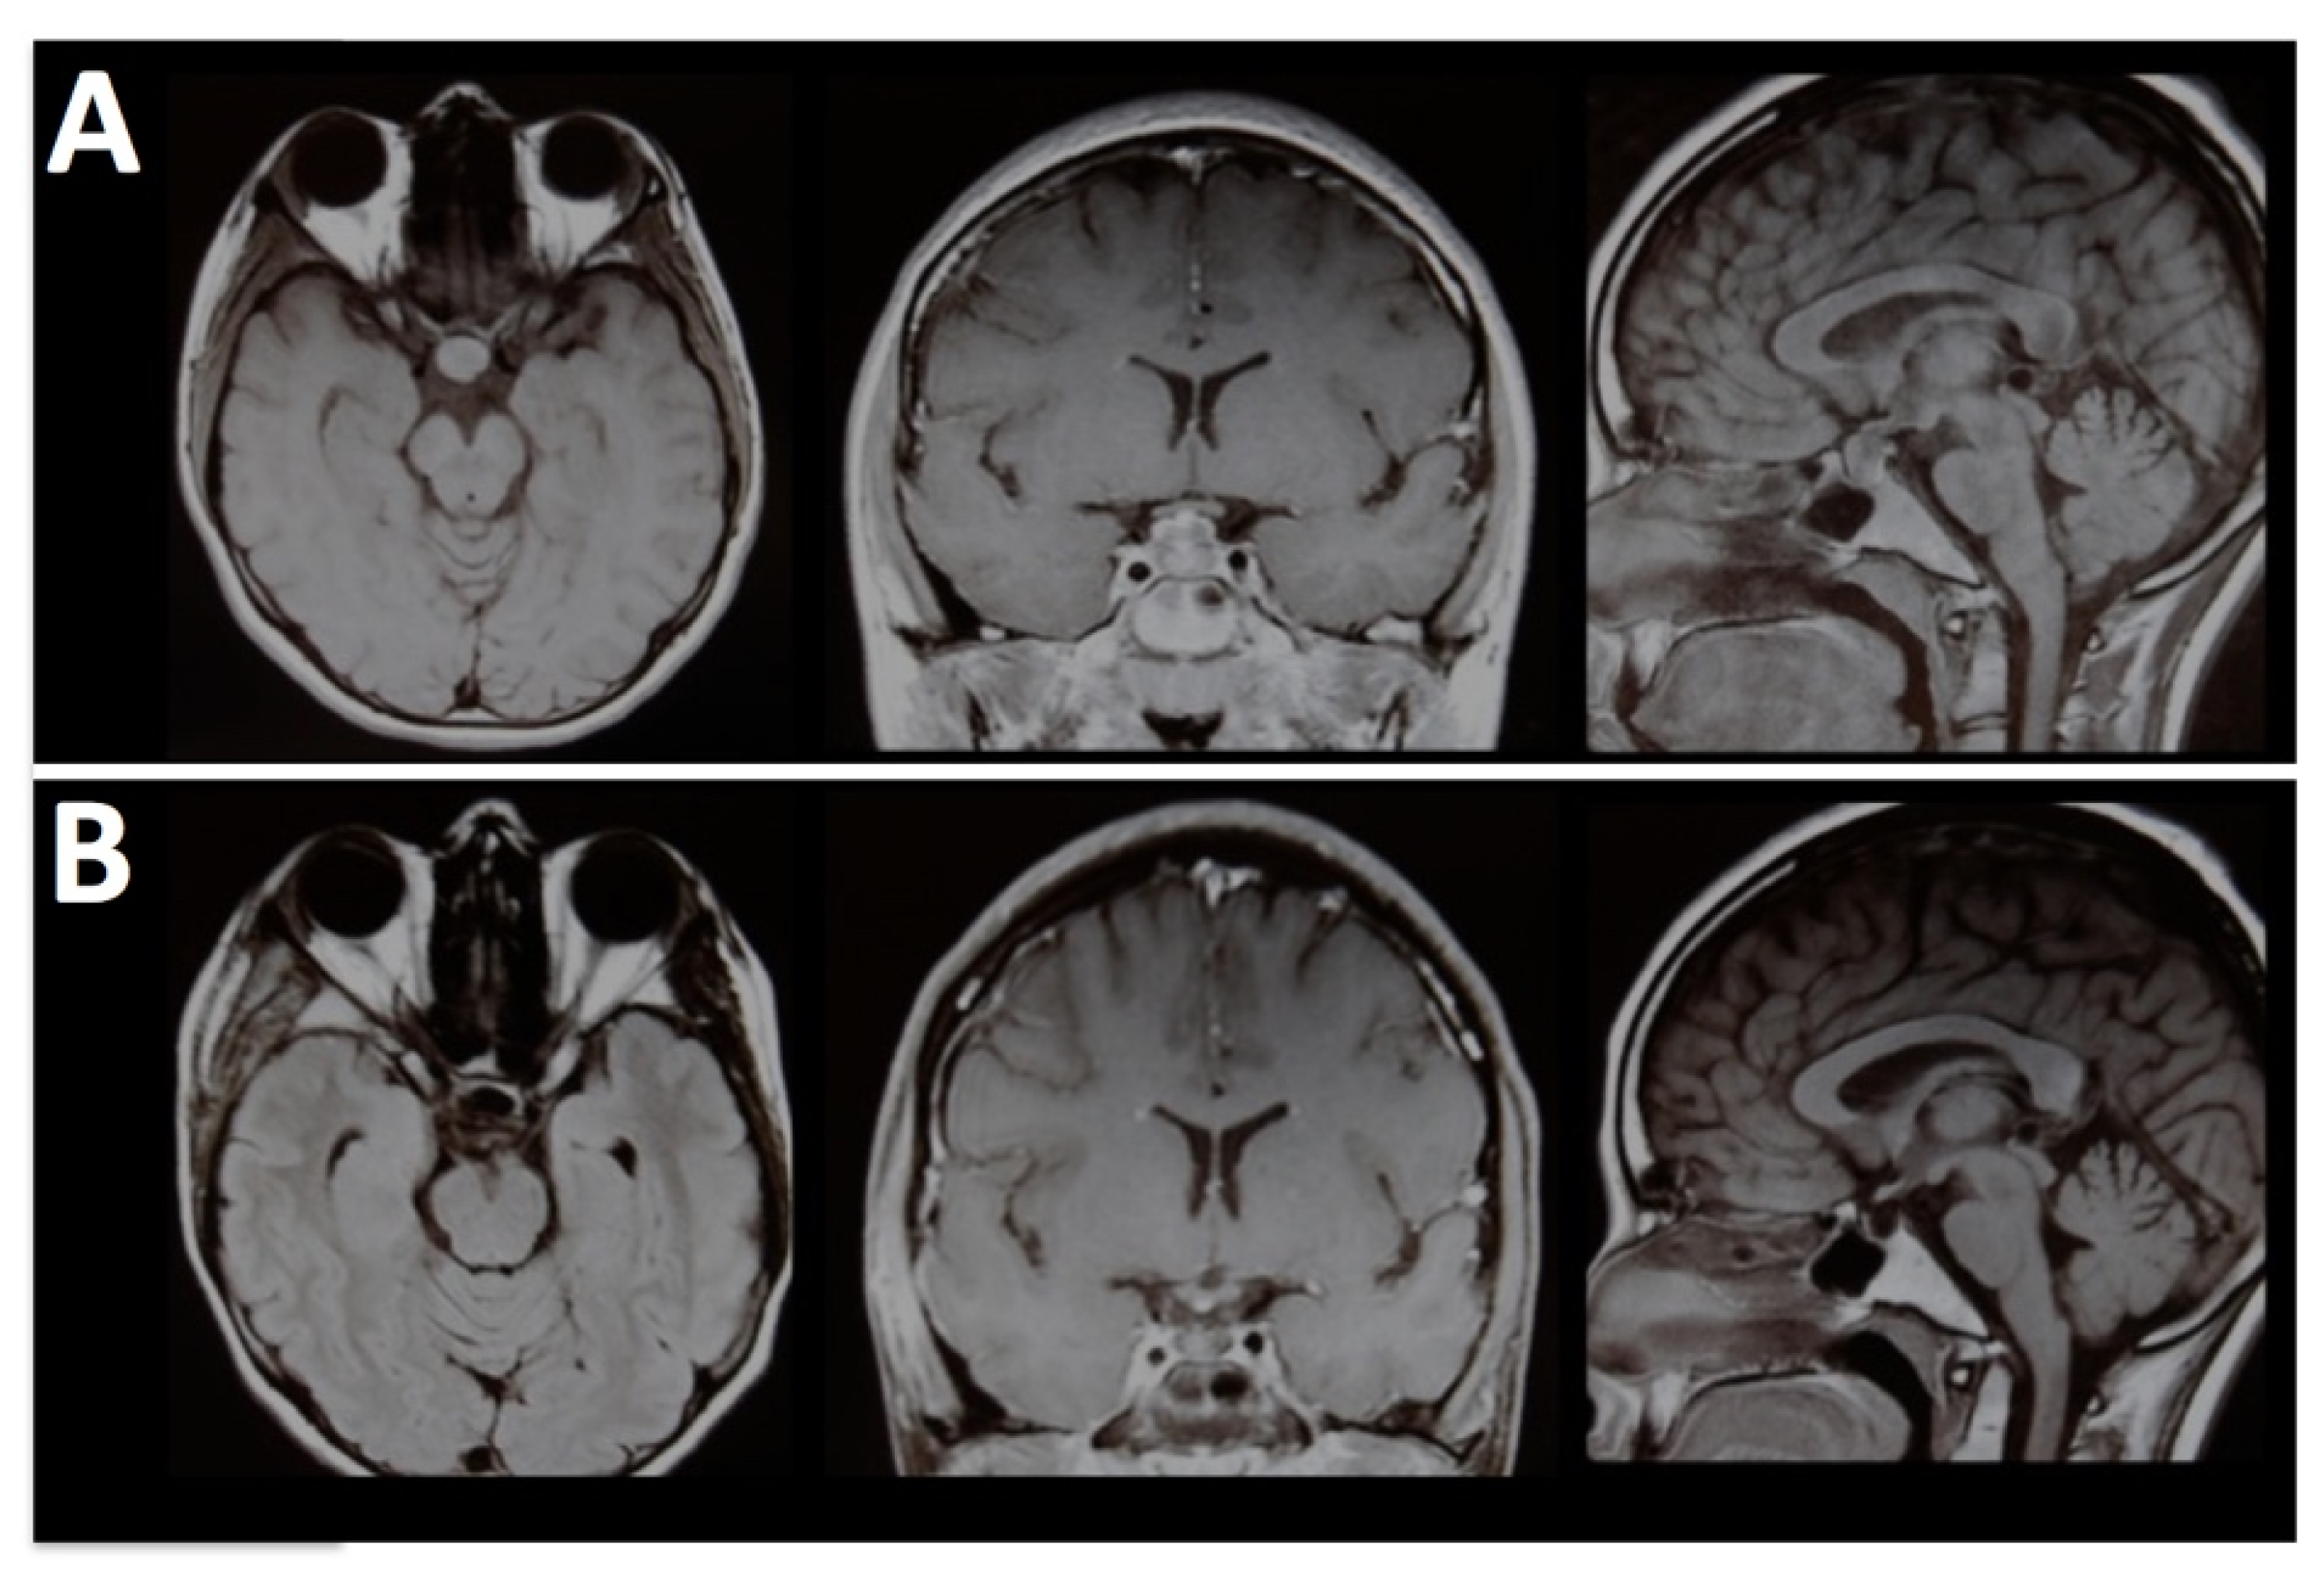

Figure 2. A 6-year-old boy was treated with orbital Ewing’s sarcoma suspicion. (A) Pre-operative MRI shows an extraconal lesion extended medially until ethmoidal cells. (B) Post-operative MRI confirms the removal of tumoral tissue.

By removing the orbital roof and lateral wall, the E-SRA technique allows for transcranial access to extraconal lesions, including those with an ethmoidal extension. This expanded access enables surgeons to reach tumors in challenging locations (Figure 2).